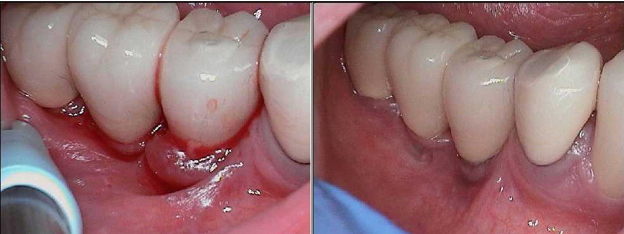

Case study courtesy of Ria Freitas, RDH

April 16, 2024: 99-year-old patient with peri-implantits​ exhibited suppuration and bleeding on #29

​PerioProtect Trays delivered 4/26/24​ at maintenance appointment after patient declined periodontal surgery.

Patient Returns for Visit on August, 19, 2024 (4 months later). Impacted food was removed on the lingual margin. Note the tissue improvement on the buccal margin.